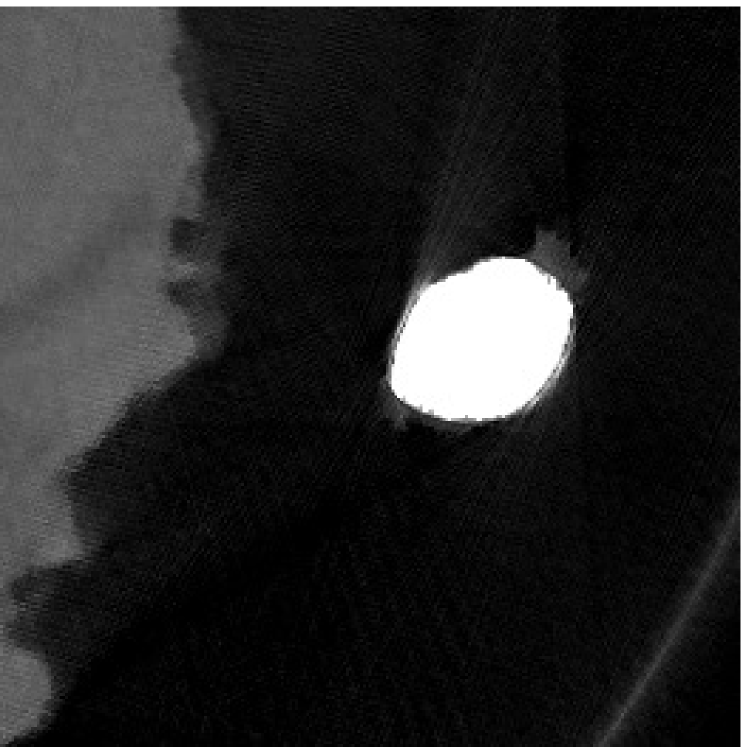

The proposed re-weighted JSR model requires a pre-estimation of the metal trace and weights in projection domain. They can be obtained fairly easily from a roughly reconstructed CT image using a simple reconstruction model. In this paper, we use the tight wavelet frame based analysis model [8]. This subsection describes the details on how metal trace and weights are computed using the NURBS-based cardiac-torso(NCAT) phantom [45]. Two metal components are implanted in the NCAT phantom as shown in Figure 1(a) and the simulated projection data is obtained from a multi-chromatic X-ray source. Details on the settings of the imaging system are postponed to Section 4.1.1.

The optimization problem (2.12) can be solved by the split Bregman algorithm [29, 8] efficiently, which is also equivalent to the alternating direction method of multipliers (ADMM) [24, 26, 28]. The reconstructed phantom image by model (2.12), denoted by , is shown in Figure 1(b). Metal location in image domain can be robustly estimated by the summation of the high frequency wavelet frame coefficients (Figure 1(c)) followed by a simple thresholding. Then, the index of the metal trace in Radon domain, denoted by , can be identified by the projection of the indicator function associated to the metal location (Figure 1(d)).

The NCAT phantom (shown in Figure 1(a)) and the cerebral phantom111http://see.xidian.edu.cn/vipsl/database_CTMR.html (shown in Figure 8(a)) are chosen as image phantoms. For the NCAT phantom, it has pixels. Two metal components (Titanium) are implanted in the image, which is shown in Figure 1(a) with red curves labeling the locations of the metals. For the cerebral phantom, it has pixels and three metal components (Titanium) are implanted. Both of the phantoms contain three major components, i.e. soft tissue, bone and metal components, and their linear attenuation coefficients can be found in [30].